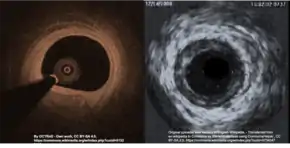

Intracoronary imaging (ICI), consisting of intracoronary optical coherence tomography (OCT) and intravascular ultrasound (IVUS) can help distinguish SCAD from an atherosclerotic lesion when it is difficult to do so with angiography.[16] ICI techniques provide a direct view of the walls of the coronary artery to confirm SCAD, but may actually worsen the dissection as the probes are inserted into the damaged area.[4] ICI confers a 3.4% risk of iatrogenic dissection in people with SCAD compared to 0.2% risk in the general population.[4] Between the two ICI methods, OCT - a newer technique - has superior spatial resolution than IVUS and is the preferred technique if ICI is required,[4] but the need to inject extra contrast with OCT poses risk for worsening the dissection.[11]